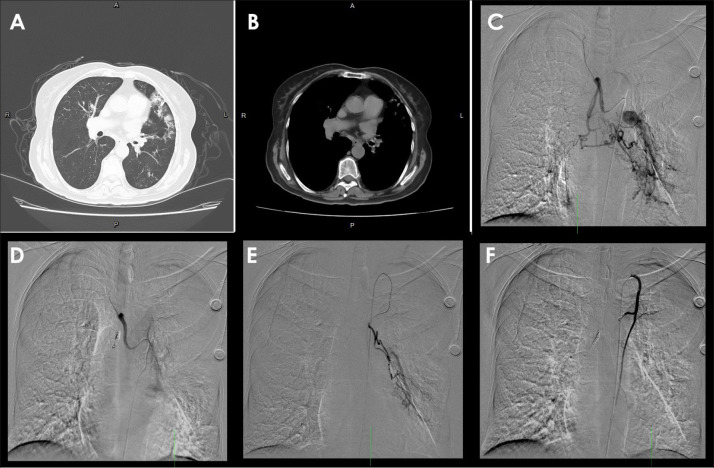

Abstract Image